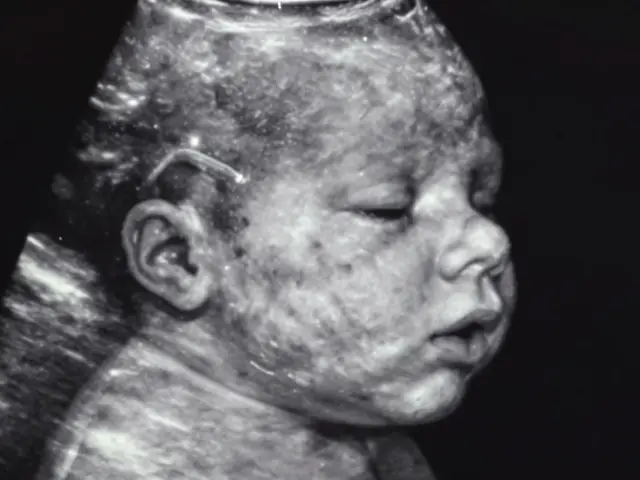

Co je vidět na ultrazvuku v 5 týdnu těhotenství?

Co je vidět na ultrazvuku v 5. týdnu těhotenství? Plodový sac, možný pohyb embrya, začínající srdce. Víte, co je normální a co ještě příliš brzy? Všechno, co potřebujete vědět.